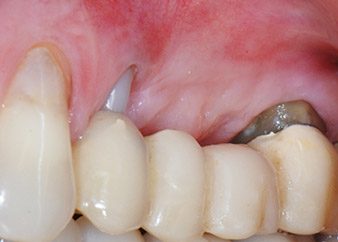

Mujer de 58 años de edad, que además es una apreciada colega y amiga, y se quejaba de dolor y de un aumento en la movilidad del pilar del puente de la pieza dental 24. También había inflamación periodontal, con bolsas de una profundidad de 7 mm en sentido mesiobucal y más de 12 mm en sentido distal, así como furcación de tercer grado. Asimismo, la radiografía reveló una lesión periodontal extensa alrededor de la región apical de la pieza dental 24 (figura 1) tratada previamente con endodoncia (alio loco).

Un mes después, en el día de la intervención, el dolor y la inflamación se habían reducido al mínimo en la pieza 24, pero seguía habiendo una movilidad de clase II de Miller. Después de la apertura de los colgajos y de la limpieza del tejido infectado periapical y perirradicular, la extensión del defecto óseo quedó evidente (figuras 2 y 3).

En la raíz bucal, faltaba todo el hueso vestibular y distal. Básicamente, la fijación se limitó a la raíz palatal, lo que corroboró el mal pronóstico preliminar. La pieza 27 también mostró una fijación horizontal reducida (figura 12) y una rarefacción apical mínima (figura 1), si bien sin síntomas clínicos.